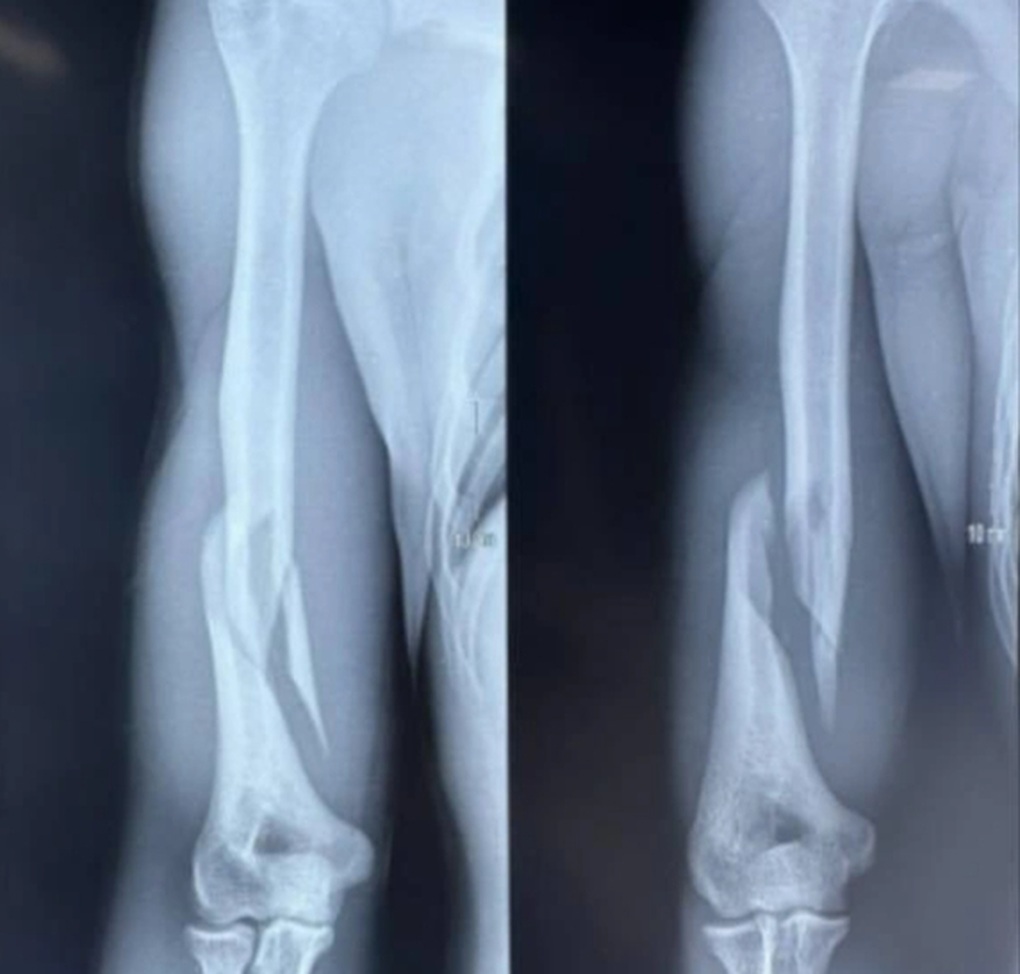

Phim X-quang của bệnh nhân cho thấy gãy phức tạp 1/3 dưới xương cánh tay phải. Đây là ổ gãy điển hình của tổn thương xương cánh tay do vật tay (Ảnh: Bệnh viện cung cấp).

Bệnh nhân được chỉ định phẫu thuật kết hợp xương cánh tay bằng nẹp vít. Phim chụp X-quang sau mổ cho thấy ổ gãy phức tạp được kiểm soát tốt, đủ vững chắc, trục chi và chiều dài chi đạt, tạo điều kiện tốt cho phục hồi chức năng sau mổ.